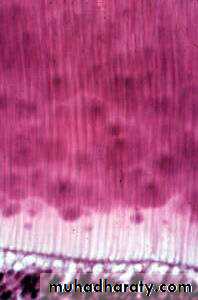

PredentinGround Section Of D. Ts.

Ground section

Neumann’s sheathOdontoblastic process (Tomes’ fiber)

Periodontoblastic space

Scanning microscopeDecalcified section